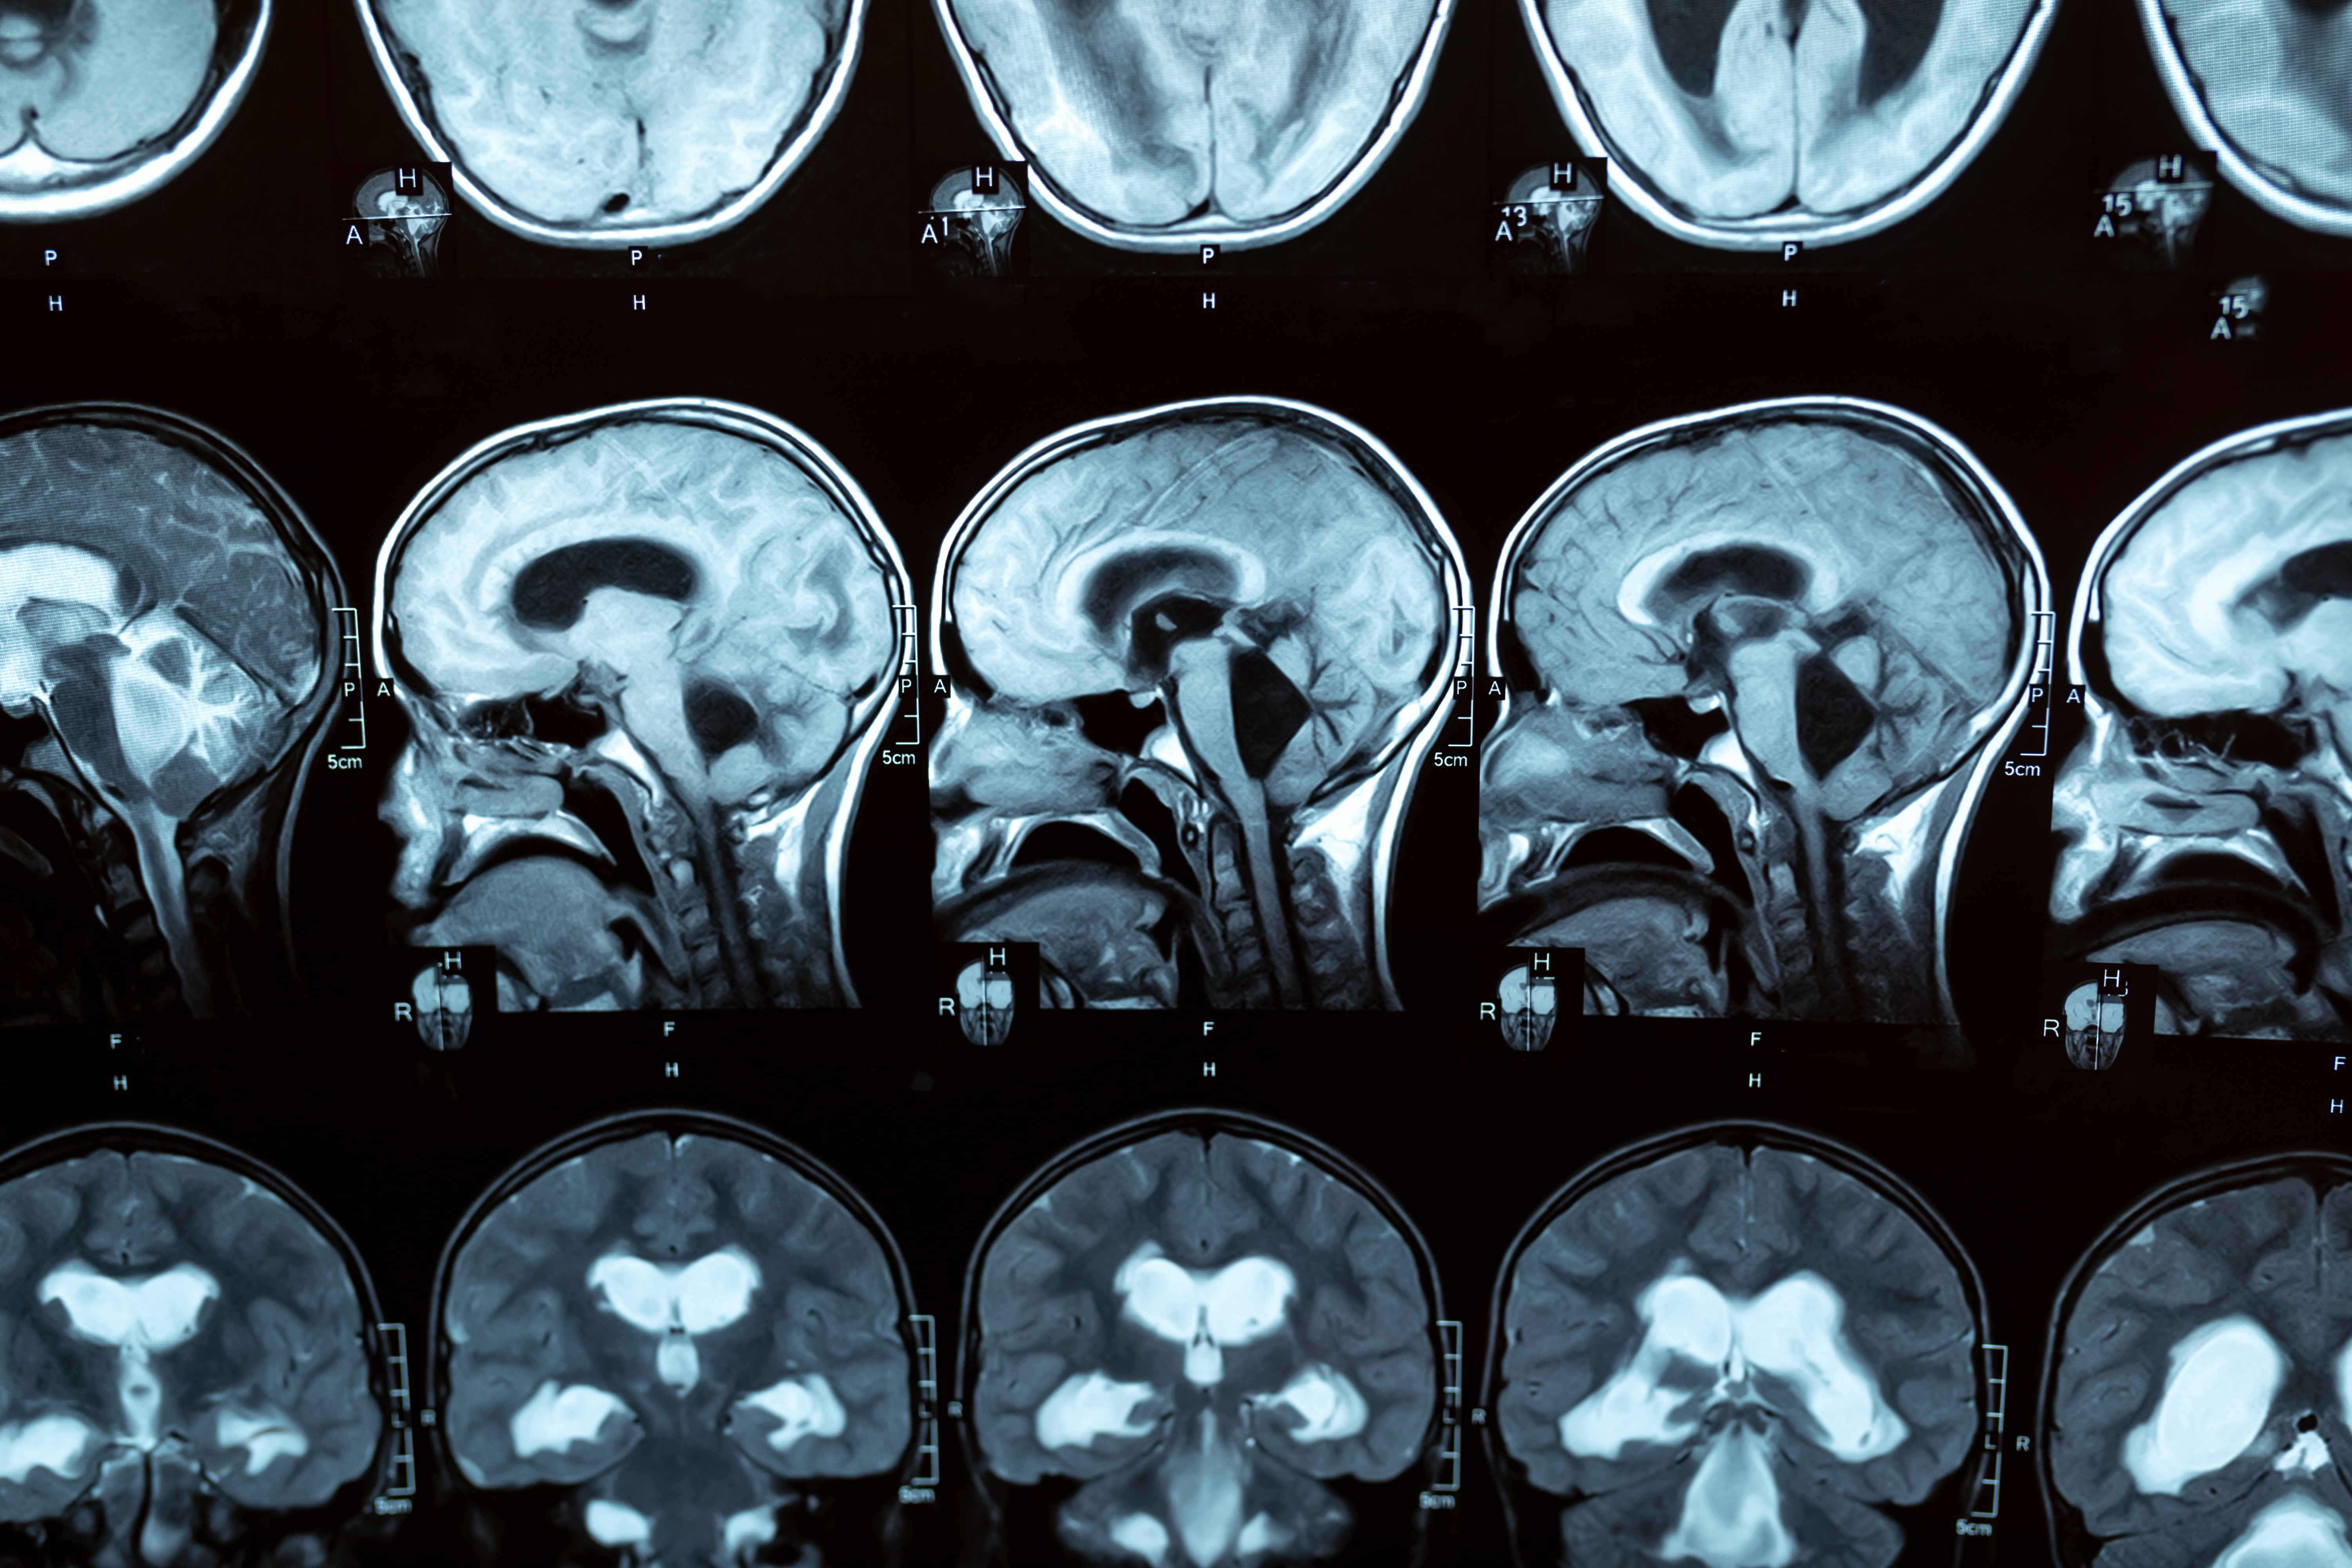

Les fuites de LCR ont des effets connus : ces fuites sont associées à une diminution de la flottabilité du cerveau et à un affaissement cérébral visible à l’IRM. Un affaissement cérébral sévère peut entraîner des symptômes très similaires à ceux de la démence frontotemporale, un type de démence précoce. De précédentes recherches ont ainsi révélé qu'un type de fuite spinale du LCR appelé « Fistule LCR-veineuse » est fréquent chez les patients présentant des symptômes de démence frontotemporale. Une fois identifiée grâce à une technique d'imagerie spécialisée (myélographie par soustraction numérique), la fuite peut être chirurgicalement corrigée ce qui résout en général les symptômes de démence.

Combien de patients déments concernés ? Des fuites de LCR sont identifiées chez environ 1 à 3 % des adultes ayant subi un traumatisme crânien. Les symptômes de fuites graves de LCR comprennent des maux de tête, un déséquilibre et une hypersomnolence. Bien que de nombreuses fuites de LCR puissent se résoudre d'elles-mêmes, des fuites plus importantes peuvent nécessiter une ligature chirurgicale via une procédure mini-invasive. Identifier la source des fuites de LCR peut être complexe mais il existe aujourd’hui des technologies d'imagerie pour y parvenir.